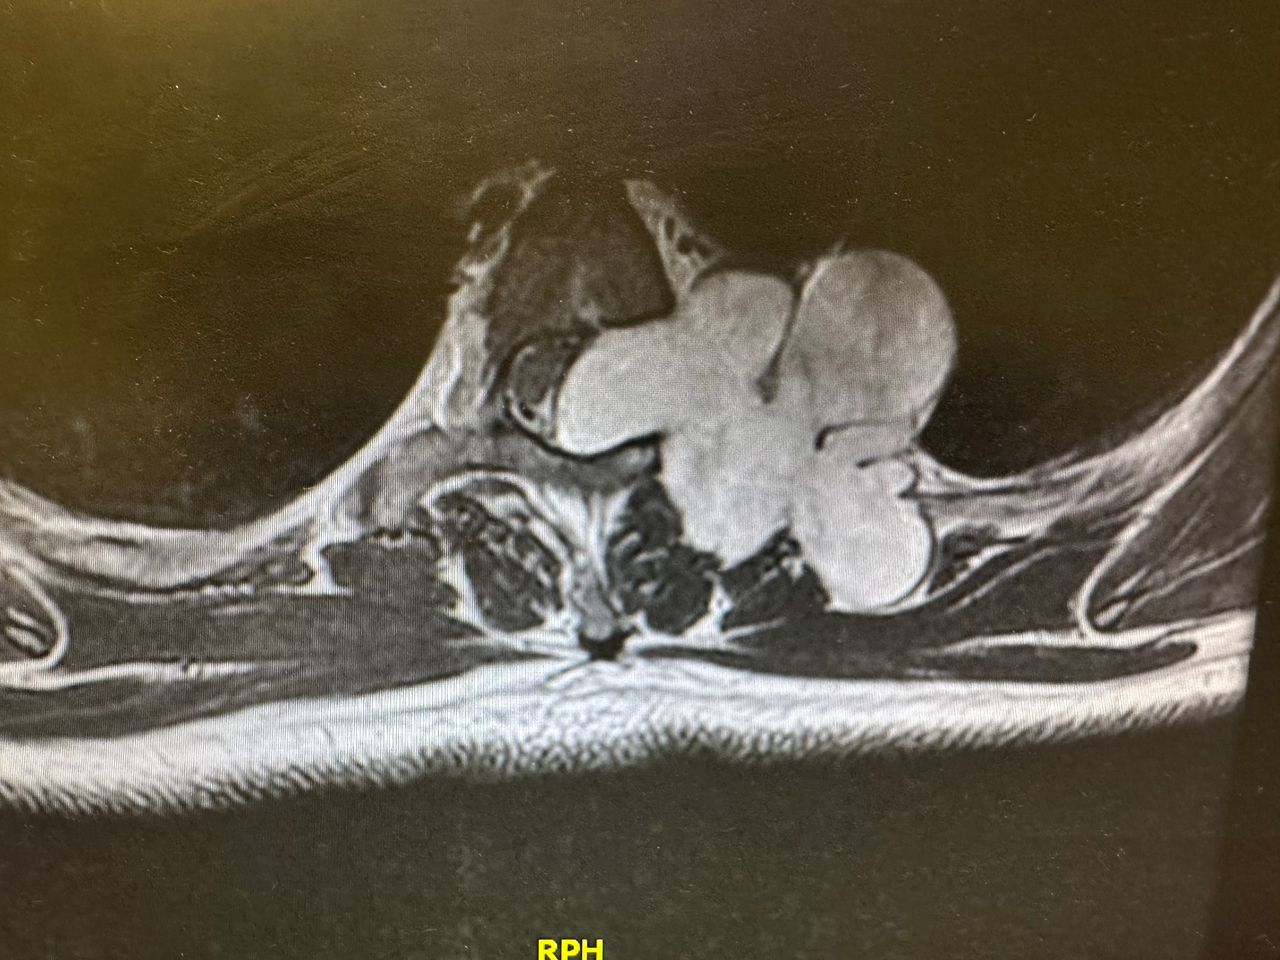

- Microchirurgia vertebrale

Microchirurgia dell’ernia cervicale e lombosacrale con con dimissione entro 24-48 ore

Microchirurgia stenosi del canale vertebrale, stenosi foraminali

- Microchirurgia dei tumori spinali